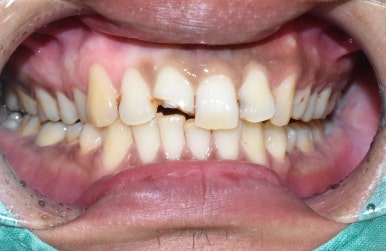

방금 넘어져서 앞니가 깨졌다며

잘하는 치과 수소문해서 소개받고 오신 외국인환자분입니다.

앞니깨짐

처음에는 크라운을 하면 될거라 예상했지만

자세히 보니 앞니가 뿌리 부분까지 쪼개져서 벌어져 있었습니다.

발치해서 보니 위와 같이 잇몸 깊은 곳까지 두동강 나 있어서

살리기 힘든 상태였습니다.